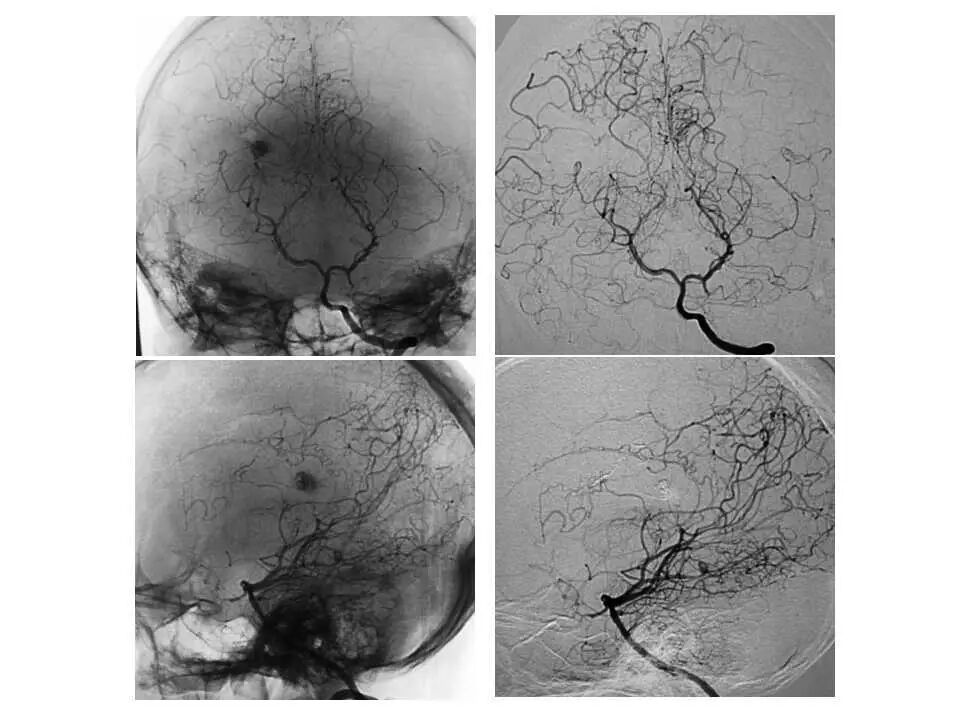

今天为大家分享的是“强生医疗CNV-神经介入专栏”第十五期,由首都医科大学宣武医院何川教授带来的“颅内动脉瘤介入治疗”精彩讲课视频及PPT,欢迎观看、阅读。文章仅代表作者个人观点,如有不同见解,欢迎同道斧正!

何川 ,首都医科大学宣武医院副主任医师,中国医师协会神经介入专业委员会常务委员,长期从事脑血管病和脊髓血管病的手术及介入治疗和相关研究工作。首都医科大学神经外科博士,师从于中国神经介入开创人凌锋教授;日本东北大学医院脑血管病治疗科博士后,师从于日本国脑血管病血管内治疗的开创者高桥教授。